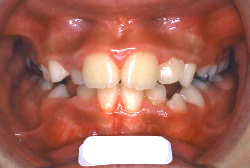

「受け口」という主訴で来院したケースです。乳歯列期の反対咬合は、ほぼ間違いなく「骨格性の反対咬合」です。骨格性というのは、歯の位置に問題があるから反対咬合になっていると言うことではなく、骨の大きさと形に問題がある、つまり発育の異常が原因であると言うことです。

上顎前方牽引装置で3歳から4歳にかけて治療した一例です。早ければ6ヶ月くらいで、上の歯が外側に来た状態で噛めるようになります。この装置は、上顎の発育を助け、下顎の発育を抑制する効果があるので、上顎骨の発育不良を伴うケースに最も効果的です。

矯正歯科というと歯並びを直す医者というイメージですが、欧米では矯正歯科医=顎骨整形医と考えられていて、顔の発達を正常にする医者としての役割が重要とされています。日本ではこの面がおろそかにされていることが多く、乳歯列期に反対咬合を見つけても、多くの歯科医師がまだ小さいから様子を見ましょうというアドバイスをしてしまい、一番良い治療のタイミングを逃してしまうことが多々見られます。小児の反対咬合は、まずは矯正歯科の専門医に診せてください。早いお子さんですと3歳くらいから治療の対象になり、早く対応すればするほど簡単に治すことができます。